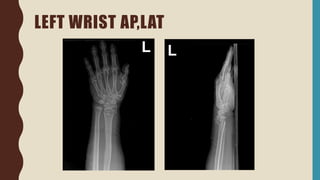

LEFT WRIST AP,LAT

MANAGEMENT

• Hematoma block

• Close reduction

• On AP short arm slab

CLOSED FRACTURE AT LEFT DISTAL END RADIUS

FRACTURE (COLLES’ FRACTURE)